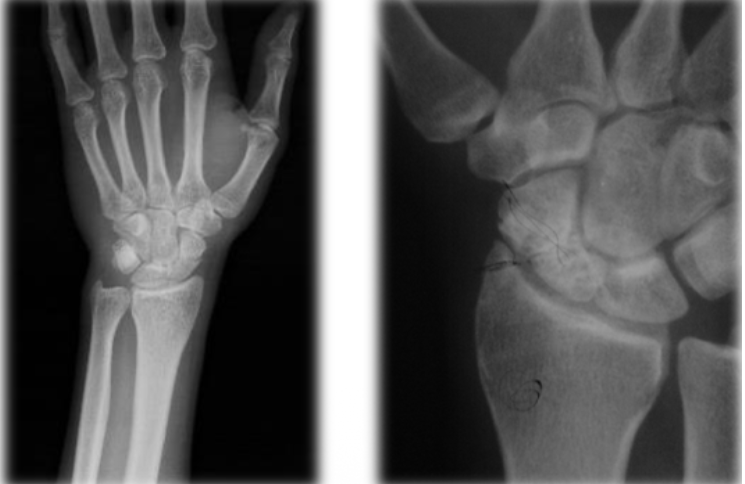

En un paciente con una fractura con esta radiografia, que tratamiento se recomienda?

Clavillos + yeso, fijador externo o placas

Fractura que se presenta en esta radiografia

Fractura de Smith